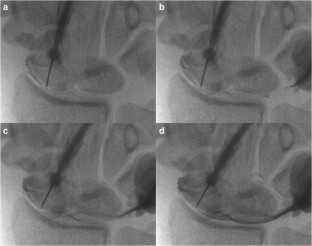

Fig. 1

Fig. 2

Fig. 3

Fig. 4

Fig. 5

Fig. 6

Fig. 7

Fig. 8